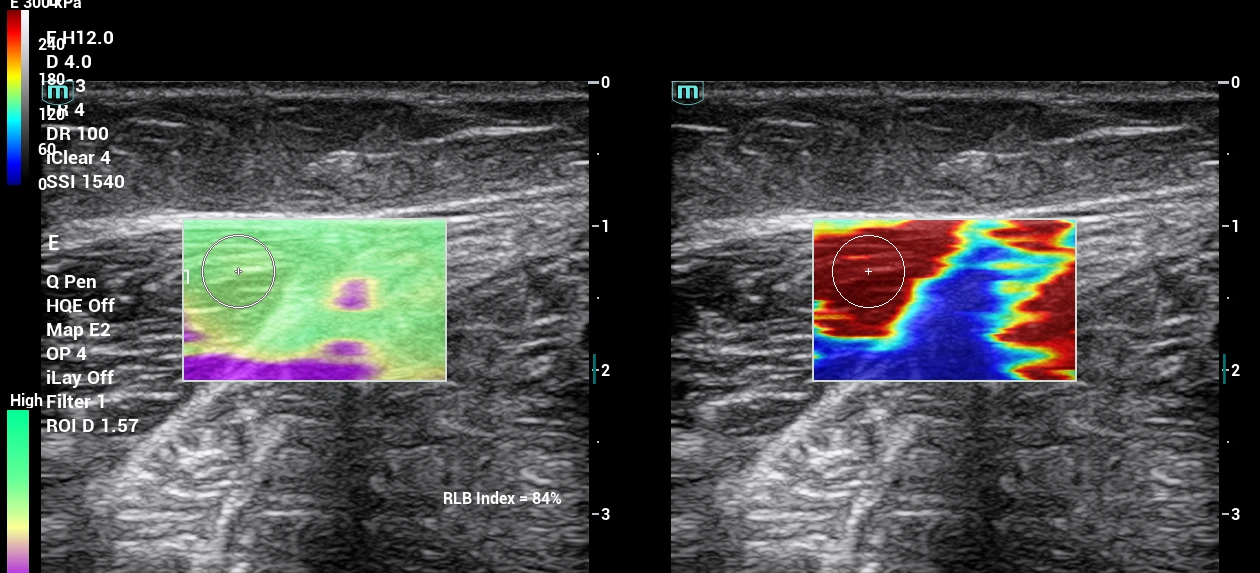

Jednou z najpodstatnejších je inovácia v diagnostických postupoch pri vyšetrení a ošetrení svalových štruktúr v oblasti celého tela, panvy a svalov panvového dna. Objektivizáciou funkcie svalov panvového dna a vybraných svalov trupu prostredníctvom 2D a 3D/4D ultrazvukového vyšetrenia získame komplexnejší pohľad na problém a dokážeme efektívnejšie navrhnúť vhodnú liečbu.